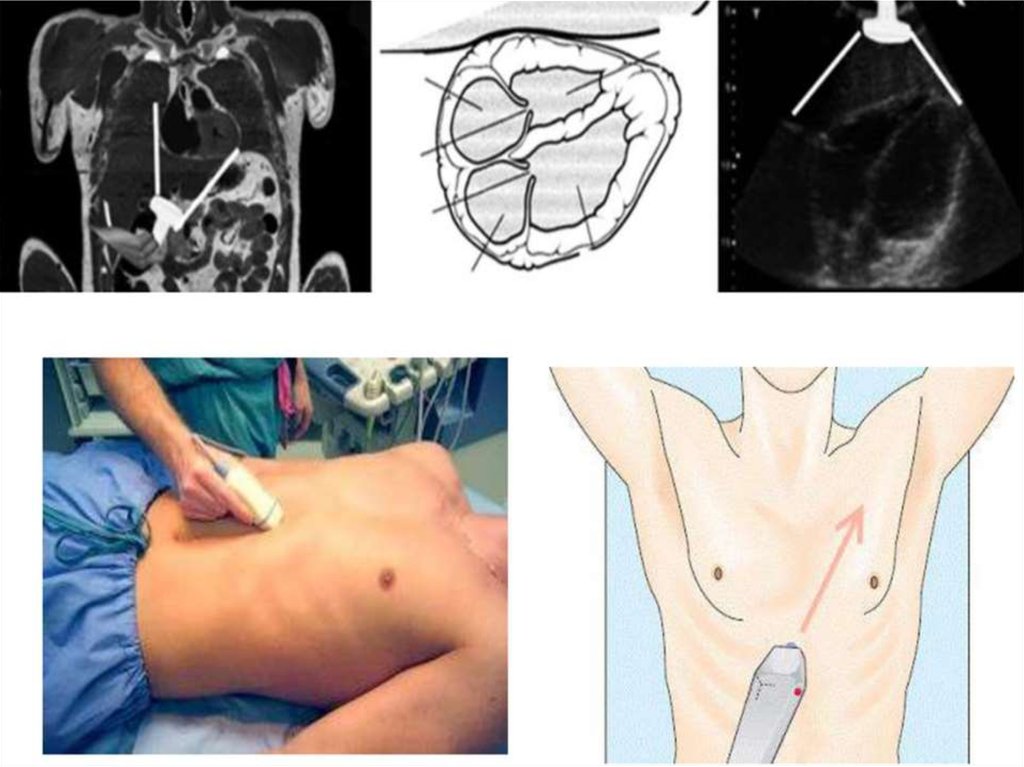

Субкостальный доступ

При FAST протоколе исследуются 8 стандартных точек: